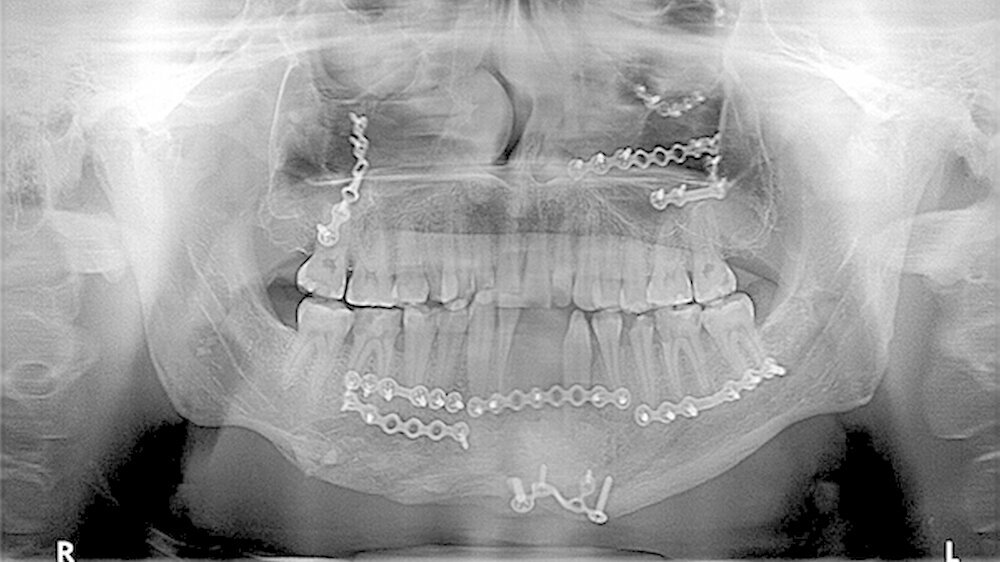

In der Folge entwickelte sich binnen fünf Monaten eine absolute Mundöffnungsbehinderung. Die SKD betrug null Millimeter. Passend zur klinischen Symptomatik zeigten sich radiologisch die Zeichen einer knöchernen Ankylose der Kiefergelenke beidseits Typ III nach Sawhney [1986] (Abbildung 1a-d).